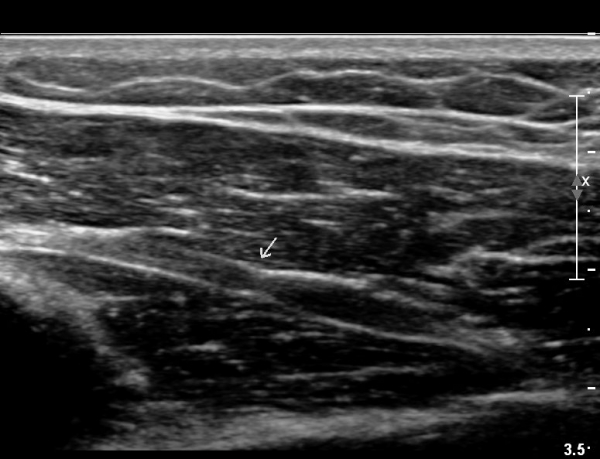

¿ä°ñ °í¶û ¸»´Ü¿¡¼ ¿ä°ñ½Å°æ Á¾´Ü¸é°Ë»ç»ó ¿ä°ñ½Å°æÀÇ Àú¿¡ÄÚ ºÎÁ¾°ú Áß°£ ºÎÀ§¿¡

±¹¼ÒÀû ÇùÂøÀÌ °üÂûµÈ´Ù(»çÁø 5).